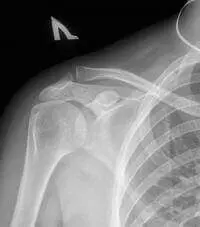

Рентген плечового суглоба у Києві на Дарниці, лівий берег ✅. Обладнання експерт класу. Мінімальне опромінення. Записатись на рентген плеча ⏩ (044) 339-90-20

Плечовий суглоб не відноситься до типових для розвитку первинного артрозу суглобів. Наявність рентгенологічних симптомів артрозу в суглобі вказує на вторинний характер змін, які є наслідком в першу чергу отримали травматичні ушкодження як в кістково-хрящової частини суглоба, так і при ураженнях навколосуглобових м’яких тканин (звапніння, макротравматізація тканин при тривалій важкому фізичному навантаженні на суглоб, деяких професійних захворюваннях, спортивної травми, при задніх підвивихах плечової кістки), а також запальних і не запальних змін в плечовому суглобі .